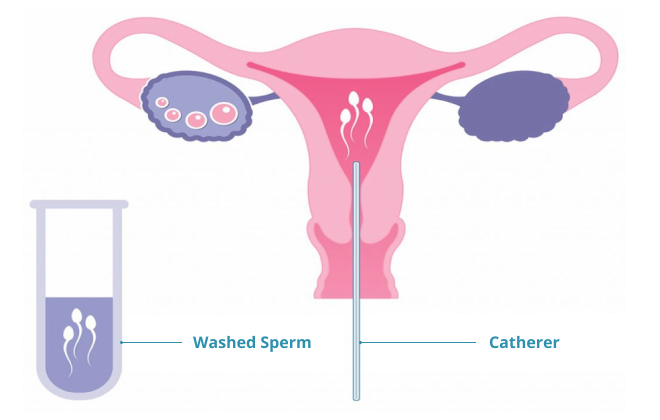

In Intrauterine Insemination (IUI), the sperm is directly placed into a woman’s uterus during ovulation to facilitate fertilization. By bypassing barriers that might prevent sperm from reaching the egg, IUI increases the chances of conception.

The sperm sample will then undergo sperm washing, which is a crucial process that serves several important purposes. Firstly, it removes impurities such as proteins and other non-sperm cells. This helps to ensure that only the healthiest and most motile sperm are used, increasing the chances of successful fertilization.

Additionally, sperm washing concentrates the sperm, further enhancing the likelihood of fertilization. Furthermore, this process eliminates any substances that could potentially cause discomfort or adverse reactions in the uterus.

The process of Intrauterine Insemination (IUI) is a simple and efficient three-step procedure:

By bypassing potential obstacles like thick cervical mucus and reducing the distance the sperm needs to travel to reach the egg, this step increases the chances of successful fertilization. Typically lasting only a few minutes, the procedure is generally painless, although some women may experience mild cramping.